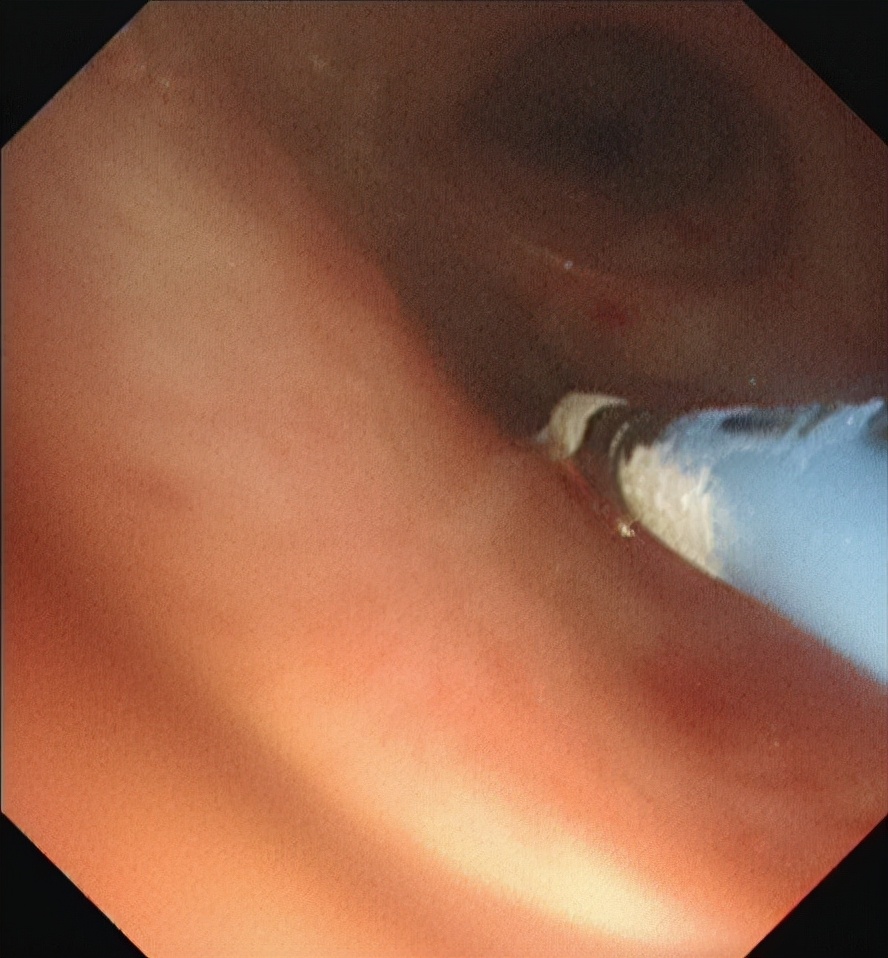

因他不愿化疗,肺内有转移灶,没有手术机会,我们再次使用气管镜下氩等离子体凝固治疗(APC)切除肿瘤,并用CO2冷冻减缓肿瘤和肉芽生长。

这次因为李先生状态不好,而且气管内肿瘤多,气道堵塞严重,手术风险高,我们团队讨论后,觉得用硬质气管镜联合电子支气管下对李先生气道内肿瘤进行切除比较安全。很庆幸,虽然手术比较难,但是手术很顺利,我们把气管内的肿物都清除干净了。切完后李先生气喘也明显好转了,最后他是自己走着出院的。